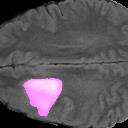

Weakly Supervised Semantic Segmentation (WSSS) relying only on image-level supervision is a promising approach to deal with the need for Segmentation networks, especially for generating a large number of pixel-wise masks in a given dataset. However, most state-of-the-art image-level WSSS techniques lack an understanding of the geometric features embedded in the images since the network cannot derive any object boundary information from just image-level labels. We define a boundary here as the line separating an object and its background, or two different objects. To address this drawback, we are proposing our novel ReFit framework, which deploys state-of-the-art class activation maps combined with various post-processing techniques in order to achieve fine-grained higher-accuracy segmentation masks. To achieve this, we investigate a state-of-the-art unsupervised segmentation network that can be used to construct a boundary map, which enables ReFit to predict object locations with sharper boundaries. By applying our method to WSSS predictions, we achieved up to 10% improvement over the current state-of-the-art WSSS methods for medical imaging. The framework is open-source, to ensure that our results are reproducible, and accessible online at https://github.com/bharathprabakaran/ReFit.